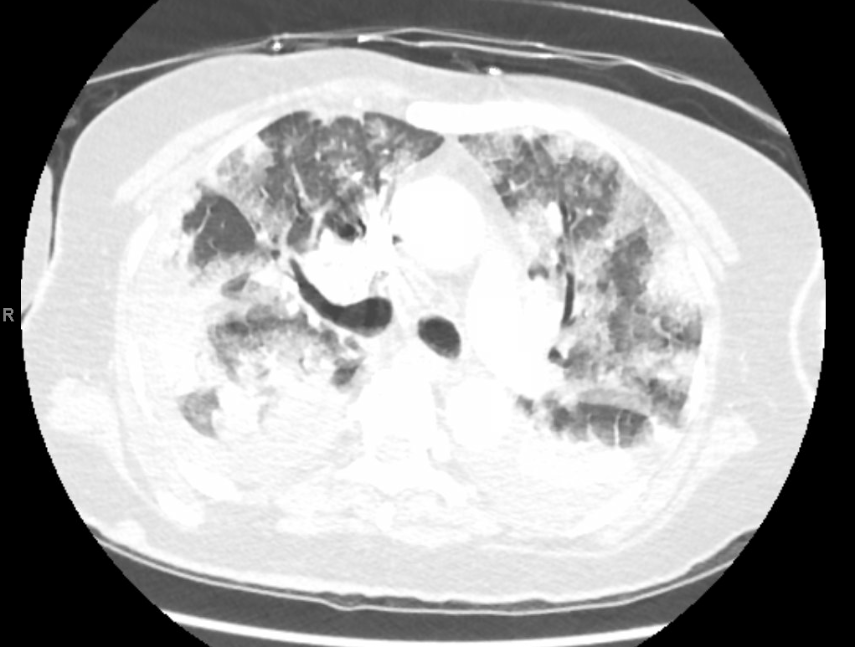

A 76 y.o. W with a past medical history of type 2 diabetes and essential hypertension, presented to hospital with a progressively worsening shortness of breath and dry cough for three weeks, which started while she was on a cruise. She had an associated rash localized to both hands, for which she was prescribed antibiotics, with improvement. She is retired from desk work and is a lifetime non-smoker. Chest xray revealed bilateral airspace disease, predominantly lower lobes, with representative CT chest above. She had a new oxygen requirement of 2L. WBC was 14.7, neutrophil predominant, absolute eosinophil count 0. Respiratory failure continued to worsen despite antibiotics. Bronchoscopy with BAL was performed, with a neutrophil-predominant cell count, normal eosinophils, and low colony count Pseudomonas aeruginosa. ANA, rheumatoid factor, anti-CCP, and DsDNA were negative. She has normal renal function. Histoplasma and blastomycosis Ab are negative. Clinical status worsens despite antipseudomonal coverage, steroids for pneumonia, and diuresis for newly diagnosed cardiomyopathy with an ejection fraction of 35%. She develops renal failure with reduced urine output, with normal urine sediment. She requires mechanical ventilation with PEEP 14, FiO2 100%. What is the next best step to establish a diagnosis?

A. Perform repeat bronchoscopy with transbronchial biopsy

B. Perform bronchoscopy with serial aliquots

C. Obtain myositis antibody panel

D. Evaluate exposures and obtain hypersensitivity panel